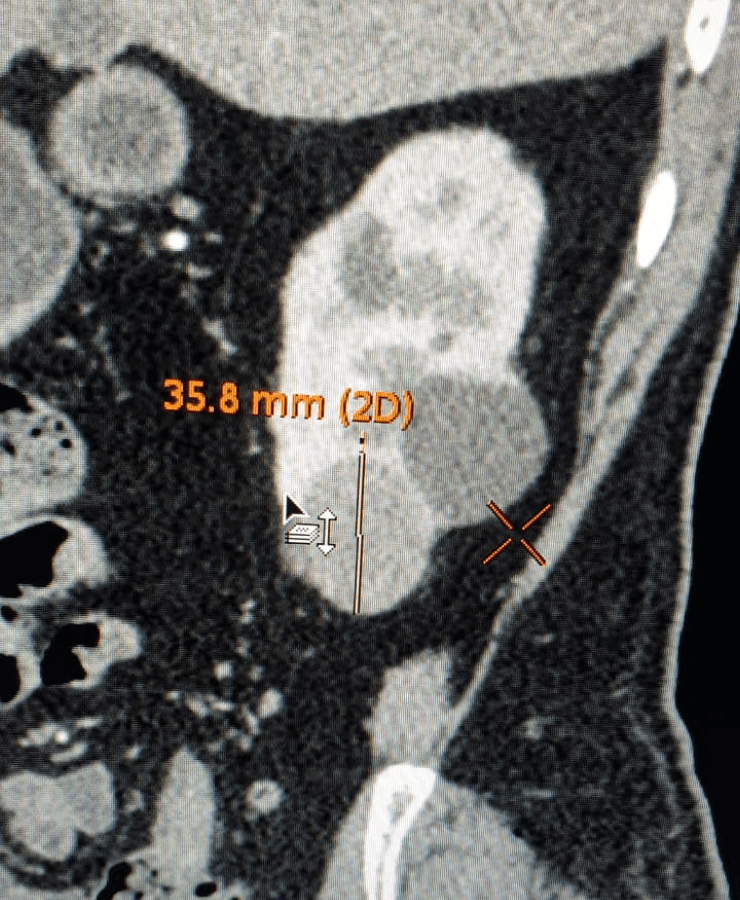

Kidney Cancer Treatment

Many cancerous tumours of the kidney, especially small or localised lesions, can be treated by thermal ablation techniques rather than open surgery, depending on patient profile and tumour characteristics.

- Radiofrequency ablation (RFA): uses controlled radiofrequency energy to heat and destroy the tumour via a needle inserted through the skin.

- Microwave ablation: delivers microwave energy to achieve rapid, predictable ablation zones, often suitable for selected renal tumours.

- Procedures are performed under USG/CT guidance to precisely target the lesion while preserving as much normal kidney tissue as possible.